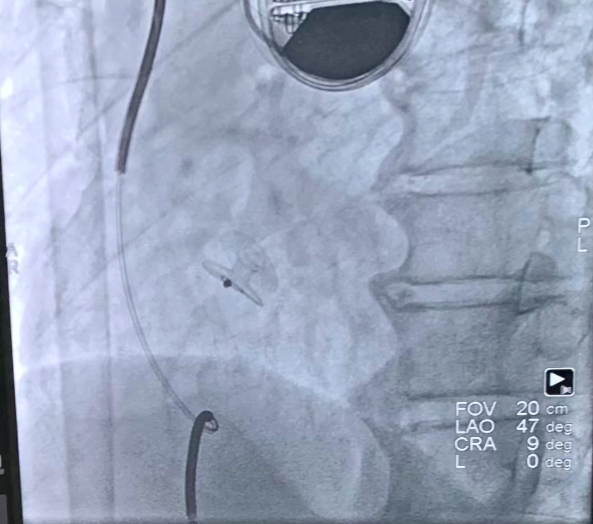

经过术前筛选排查及专家审核,认为患者存在心房分流术指征,局麻下行心房分流器植入。右心导管测量结果:肺动脉压50/34(39)mmHg,左心房压30/16(20)mmHg,右房压10/8(8)mmHg。经卵圆窝房间隔穿刺成功后送入预塑形导丝,选择6mm外周动脉高压球囊进行扩张,植入20-6心房分流器,透视及超声下观察分流器形态位置良好,测量分流器孔径约5mm,左向右分流流速1.7m/s,压差10mmHg。术后右心导管结果:肺动脉压48/32(37)mmHg,左心房压25/15(18)mmHg,右心房压6/4(5)mmHg,Qp/Qs=1.31,患者自觉症状减轻,转回普通病房。

图1:心房分流器释放到位